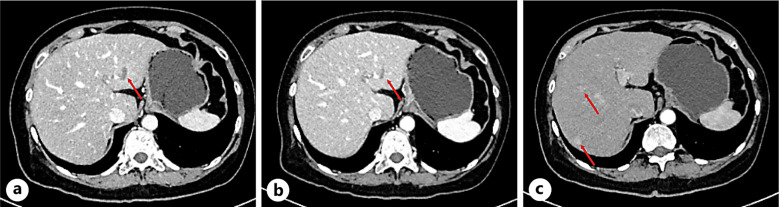

Case presentation: A 47-year-old woman was diagnosed with International Federation of Gynecology and Obstetrics stage III ovarian cancer in 2013. Between 2013 and 2021, she underwent palliative chemotherapy comprising paclitaxel liposomes, cisplatin/nedaplatin, S-1/raltitrexed, irinotecan, doxorubicin, vinorebine, toripalimab, apatinib, gemcitabine, oxaliplatin, and capecitabine, as well as two debulking surgeries. From November 2021, she received six cycles of tislelizumab (a PD-1 inhibitor), paclitaxel (albumin-bound), and carboplatin, to which a partial response was observed according to the Response Evaluation Criteria in Solid Tumors. From May 2022, the patient was switched to maintenance therapy with tislelizumab plus olaparib. However, all antitumor treatments were discontinued from April 2023 due to multiple irAEs, including hypothyroidism, adrenal insufficiency, and pneumonitis, with the tumor remaining stable until November 2023. Progression-free survival (PFS) was approximately 24 months with tislelizumab-containing therapy but was 18 months with tislelizumab/olaparib maintenance therapy.